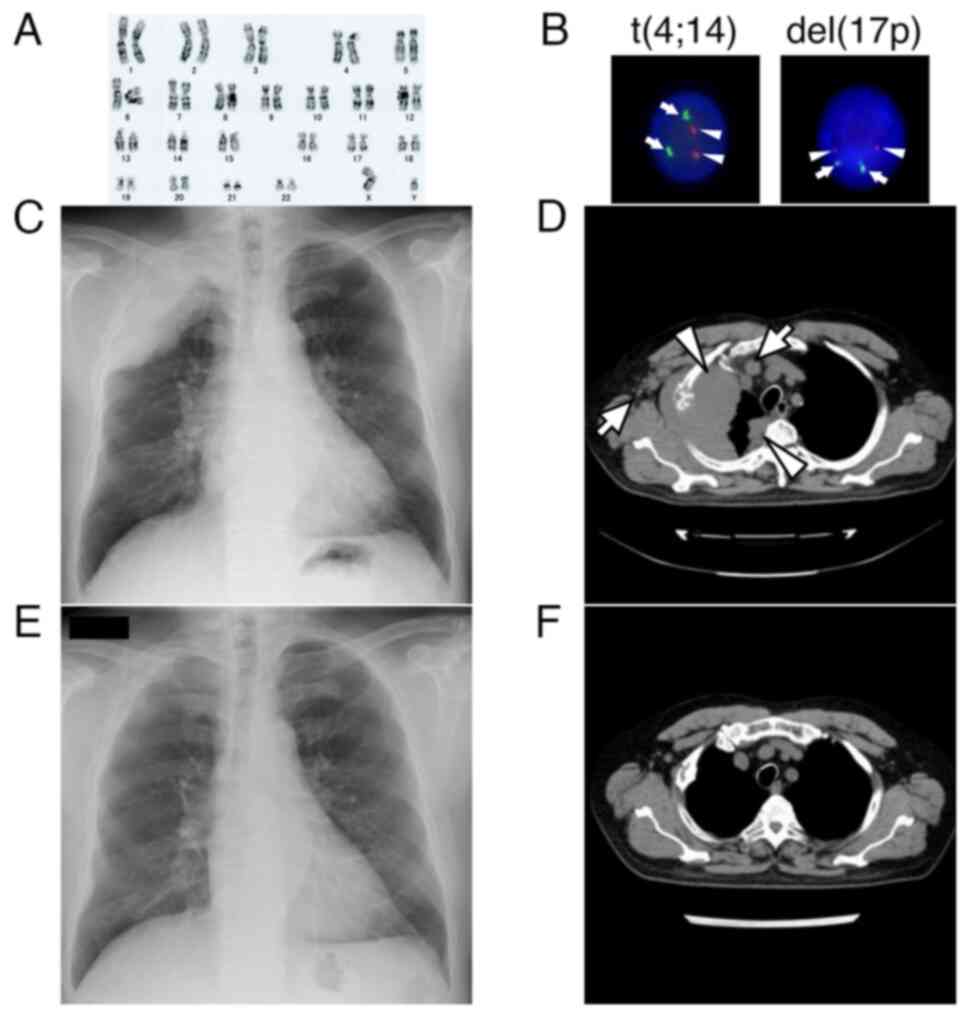

A 66-year-old Japanese male with a history of hypertension, dyslipidemia, and type 2 diabetes was referred to our hospital for multiple osteolytic tumors of the skull, ribs, and ilium. Laboratory tests revealed anemia (hemoglobin, 12.1 g/dl) and increased immunoglobulin G (IgG, 2,866 mg/dl). Serum levels of β2 microglobulin and lactate dehydrogenase (LDH) were 3.4 mg/l and 182 U/l, respectively. Immunoelectrophoresis demonstrated the presence of monoclonal component IgG κ-type. Urinary Bence Jones protein was not detected. Serum free light chain κ level was 12.2 mg/l; λ level, 3.1 mg/l; and κ/λ ratio, 3.94. Bone marrow aspirate showed 52% infiltration of monoclonal plasma cells. Cytogenetic analysis revealed a normal male karyotype (Fig. 1A) and fluorescence in situ hybridization (FISH) was negative for del(17p), t(4;14) (Fig. 1B). FISH for t(14;16) was also negative, but gain/amp(1q21) was not tested. The patient was diagnosed with stage II MM according to the Revised International Staging System (8).

Figure 1.

Results of karyotyping and FISH analysis, and radiographic images. (A) Cytogenetic analysis showing normal male karyotype (46, XY). (B) FISH analysis showing no signal for t(4;14) and del(17p). For t(4;14), the red signal (arrowheads) indicates FGFR and the green signal (arrows) indicates IGH. For del(17p), the red signal (arrowheads) indicates TP53 and the green signal (arrows) indicates D17Z1 (magnification, ×500). (C) Chest radiograph showing a massive tumor occupying the right apex. (D) Chest CT showing a bulky tumor extending to the right thorax with pleural dissemination (arrowheads). Lymph node metastases to the right axilla and mediastinum were also noted (arrows). (E) Chest radiograph on day 13 of EPd, showing marked regression of the tumor. (F) Chest CT 3 months after the initiation of EPd showing disappearance of the disease. CT, computed tomography; del, deletion; EPd, elotuzumab, pomalidomide and dexamethasone; FISH, fluorescence in situ hybridization.

Fifteen months after the initiation of DBd, severe right-sided chest pain developed, and the IgG level was elevated to 2,266 mg/dl. The lymphocyte count was elevated to 3,072/µl (Fig. 2). Lymphocytes were morphologically normal, while neither lymphocytes subset analysis nor NK cell activity was performed. Serum β2 microglobulin and κ/λ ratio were 4.5 mg/dl and 0.80, respectively. Chest radiography revealed a massive tumor occupying the apex of the right lung (Fig. 1C). A chest CT scan showed a bulky tumor arising from the right rib, extending to the right thorax, and pleural dissemination with lymph node metastasis to the right axilla and mediastinum (Fig. 1D). Neither bone marrow examination including FISH analysis nor biopsy of extramedullary mass was performed due to the patient's refusal. Upon clinical relapse of MM with extramedullary disease, the treatment was changed to EPd (elotuzumab, 10 mg/kg on days 1, 8, 15 and 22 during cycles 1 and 2, and 20 mg/kg on day 1 of each cycle thereafter; pomalidomide, 4 mg per day on days 1 through 21; dexamethasone, 40 mg once weekly) (11), which resulted in expeditious resolution of the chest pain. Notably, chest radiography on day 13 of treatment revealed marked regression of the tumor in the right apex (Fig. 1E), and serum IgG levels rapidly decreased to 492 mg/dl (Fig. 2). Three months after the initiation of EPd, a subsequent CT scan demonstrated disappearance of the disease (Fig. 1F).